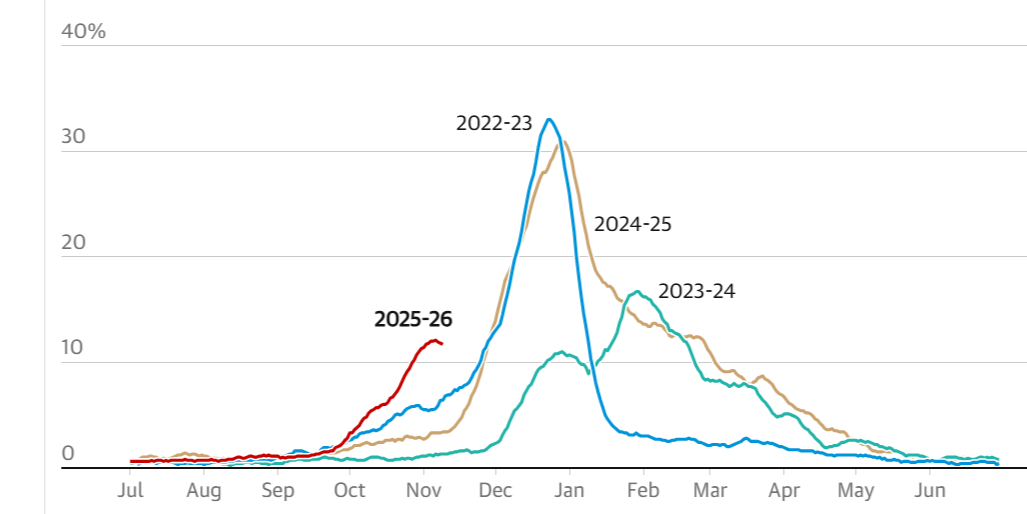

Báo cáo giám sát cúm và Covid-19 Vương quốc Anh. Ảnh: The Guardian. |

Các chuyên gia lo ngại rằng nếu những đột biến mới giúp virus né kháng thể tốt hơn, mùa cúm năm nay có thể đặc biệt nặng nề. Chủng lưu hành hiện tại là H3N2 - loại thường gây bệnh nặng hơn, đặc biệt ở người cao tuổi. Chỉ số lây nhiễm R0 được ước tính khoảng 1,4, cao hơn đáng kể so với mức 1,1-1,2 của các mùa cúm thông thường, tức 100 người mắc có thể lây cho 140 người khác.

Theo Cơ quan An ninh Y tế Anh (UKHSA), số ca cúm đang tăng nhanh nhất ở trẻ em và bắt đầu leo thang ở nhóm lớn tuổi. Làn sóng lây nhiễm được dự báo sẽ mạnh hơn khi thời tiết lạnh buộc mọi người ở trong nhà nhiều hơn.

Dù vậy, những mùa cúm do H3N2 không phải lúc nào cũng gây thảm họa. Năm 2023-2024, Anh cũng trải qua mùa cúm khởi phát sớm với một biến thể H3N2 trôi kháng nguyên, nhưng số ca tử vong (12.000 tại Anh và xứ Wales) vẫn nằm trong biên độ của các mùa cúm mạnh.